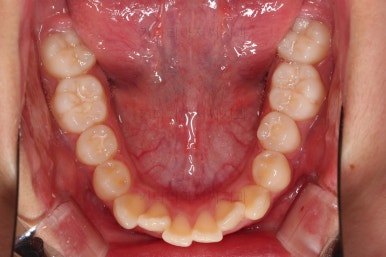

부산치아교정치과 키다리아저씨치과에서 마무리한 입안의 모습입니다.

가지런하게 잘 정렬이 되었고요.

윗니만 발치한 편악발치교정이지만 틈새 없이 공간이 닫혔으며 교합도 잘 맞습니다.

간혹 윗니만 발치를 해서 윗니만 갯수가 적어 교합에 문제가 되지 않나요? 라는 질문을 하시는 경우가 있는데요.

윗니 아랫니는 1:1로 대응 되는게 아니라 지그재그로 서로 엇갈려 있기 때문에 특히 윗니는 하나 모자라도 교합에 전혀 문제 되지 않습니다.

위아랫니가 가지런하게 보기 좋게 배열이 되었고요.

아랫니까지 윗니를 넣음으로써 튀어나와 보이던 앞니의 느낌이 좋아졌습니다.